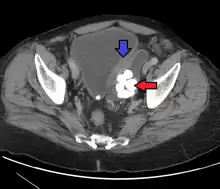

Transitional cell carcinoma | |

Other names | Urothelial carcinoma |

![]() | |

Histopathology of transitional carcinoma of the urinary bladder. Transurethral biopsy. Hematoxylin and eosin stain. | |

Transitional cell carcinoma, also called urothelial carcinoma, is a type of cancer that typically occurs in the urinary system. It is the most common type of bladder cancer and cancer of the ureter, urethra, and urachus. Symptoms of urothelial carcinoma in the bladder include hematuria (blood in the urine). Diagnosis includes urine analysis and imaging of the urinary tract (cystoscopy). Transitional cell carcinomas arise from the transitional epithelium, a tissue lining the inner surface of these hollow organs.[1] When the term "urothelial" is used, it specifically refers to a carcinoma of the urothelium, meaning a transitional cell carcinomas of the urinary system.